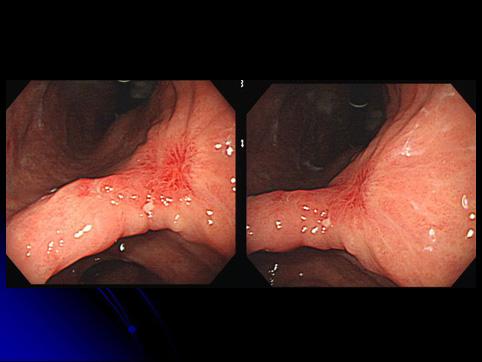

症例提示(所在地,施設名等): 福岡県・ 国家公務員共済組合連合会 浜の町病院 (松浦隆志先生からの提供症例)

疾患(病理主体)の分類悪性上皮性腫瘍/腺癌

部位(臓器別)胃(部位)/胃角

検査方法内視鏡

腫瘍の肉眼分類0型(表在型)/IIc型(IIc)

病変の最大径(ミリ)35〜40

腫瘍の深達度m